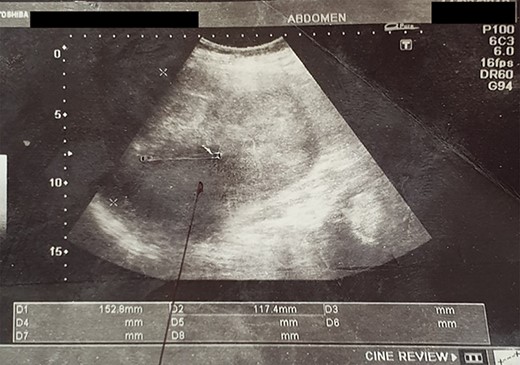

An abdominal ultrasound (US) revealed a 12 × 12 cm solid mass from the left suprarenal area (Fig. 1). Contrasted computed tomography (CT) revealed a 17.5 × 11.5 cm enhancing lesion in the left suprarenal region, completely replacing the left adrenal gland. The left kidney was inferiorly displaced, and coarse calcification was seen at the lesion’s periphery without lymph node enlargement. The contralateral adrenal gland, retroperitoneal and peritoneal structures were normal (Figs 2 and 3). Screening for primary carcinomas presenting as adrenal deposits utilizing clinical examination, pan endoscopy and contrasted CT were all negative. At this point, our working diagnosis was non-secreting left pheochromocytoma, and elective laparoscopic left adrenalectomy was planned.